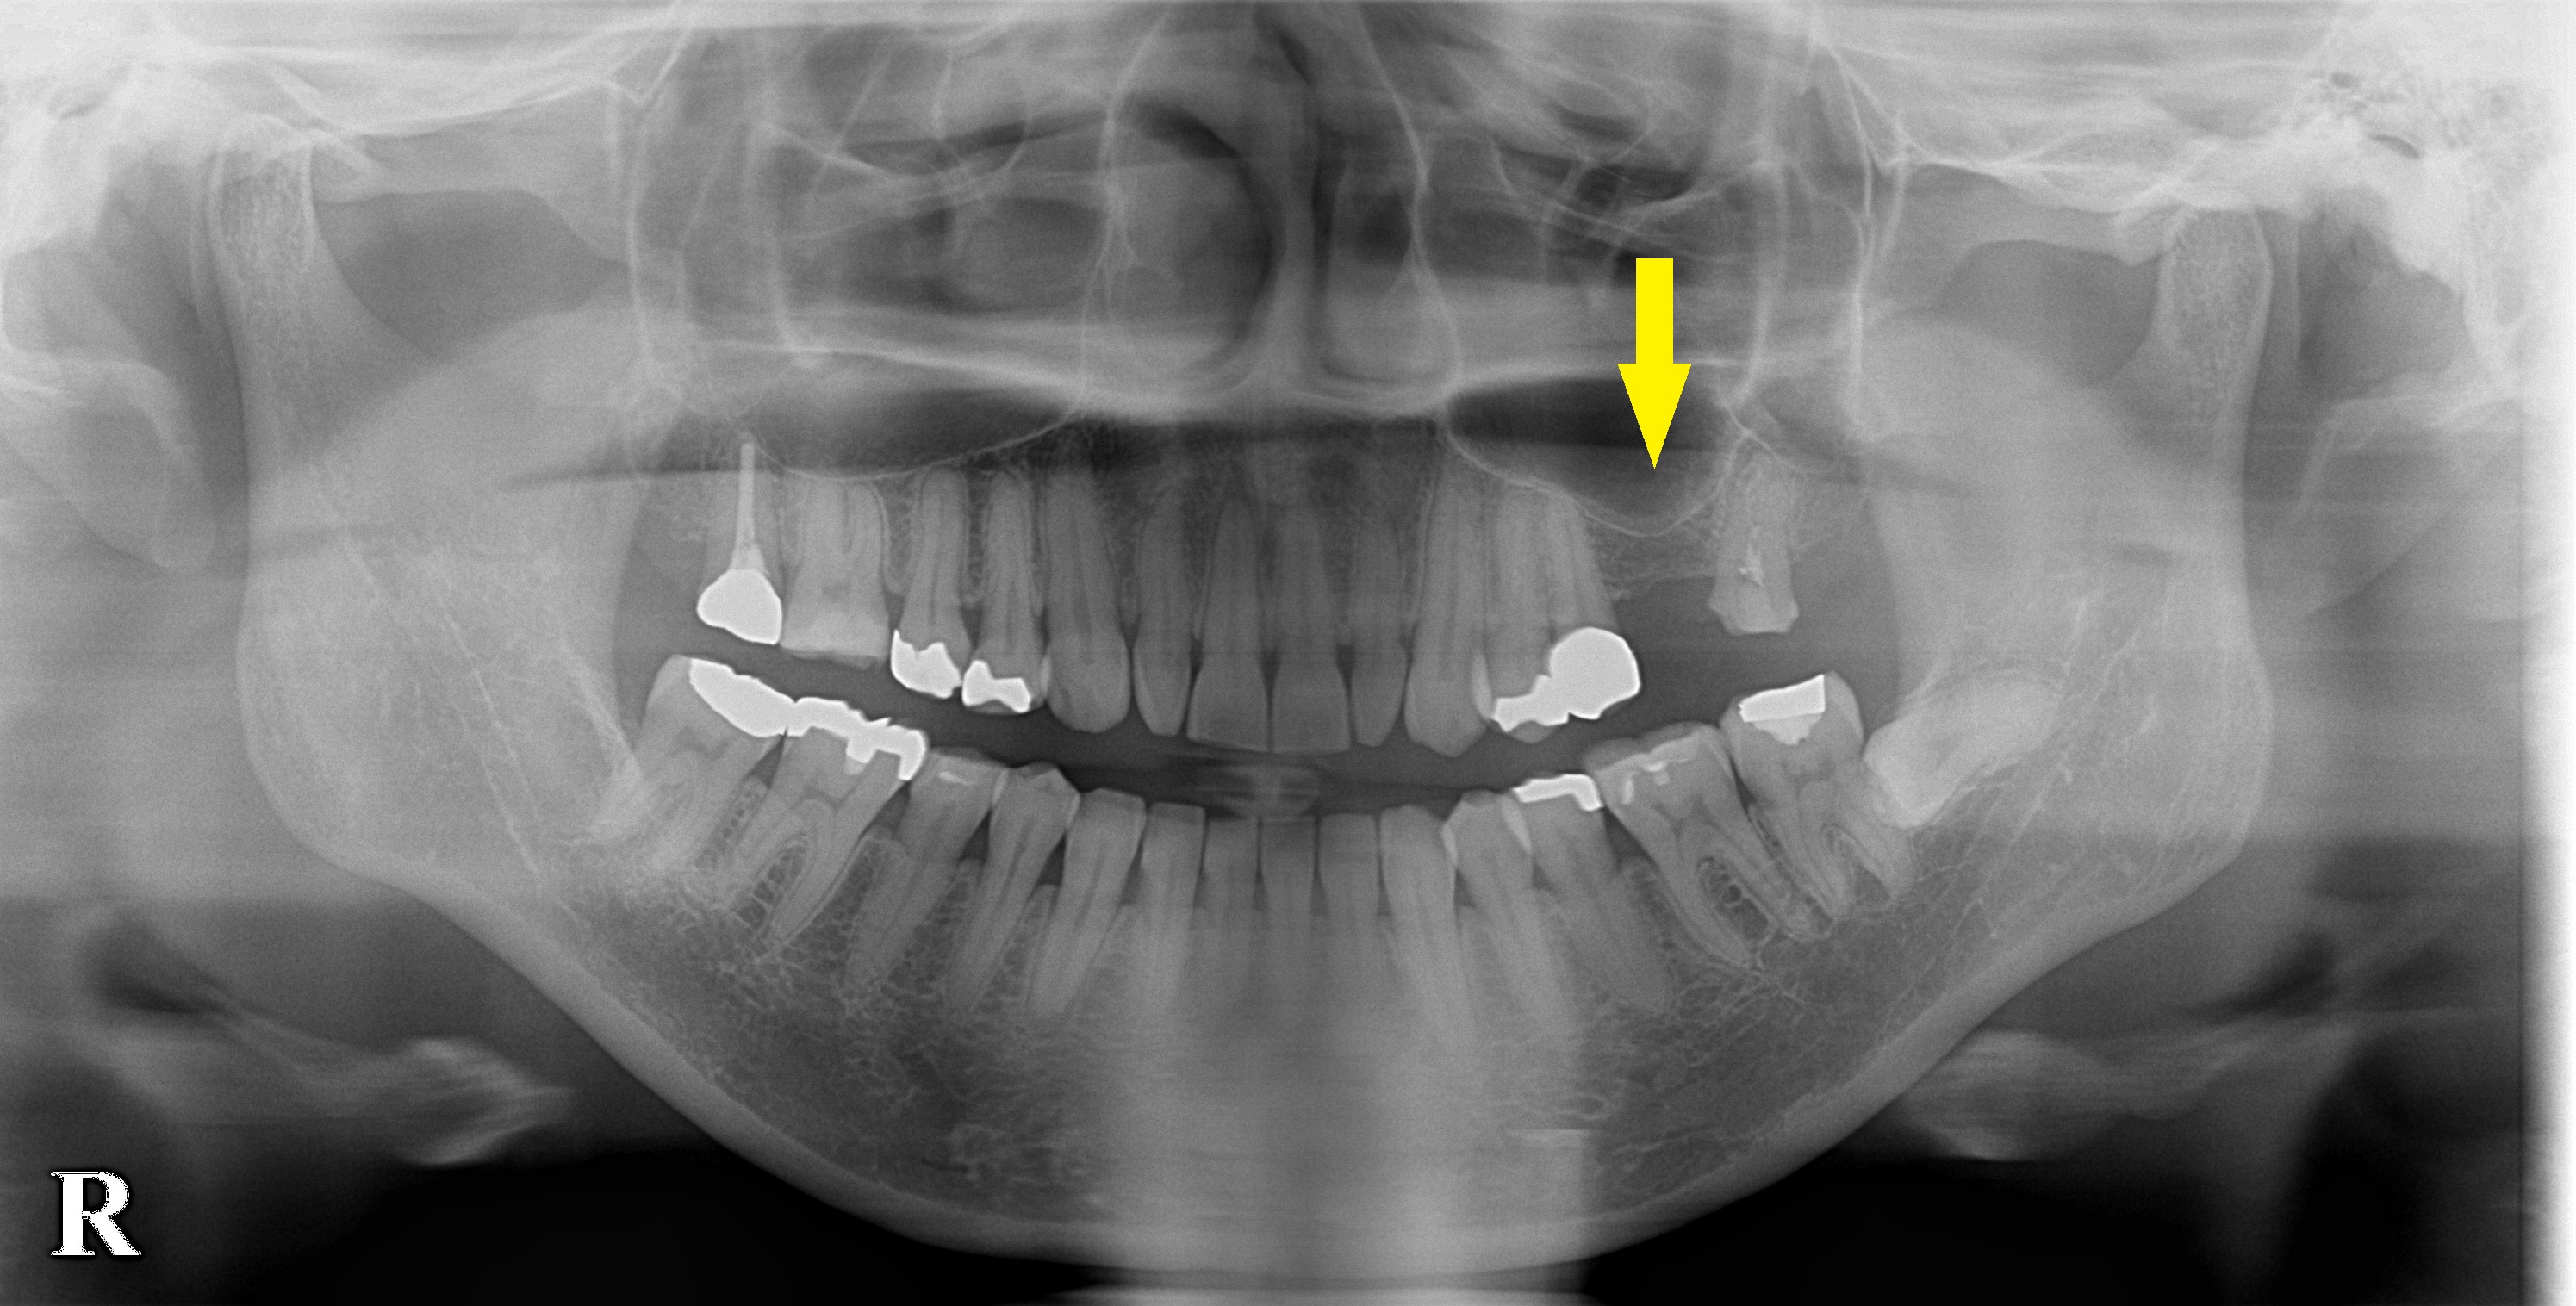

CTを撮影してみると、方向によっては、骨がありそうに見えますが、やはり十分な骨量とはいえませんでした。

ある程度の骨はありますので、ワイドインプラントを用いて、人工骨は使用せず、骨造成も行わないで、インプランント埋入が可能であると説明させていただきました。

下の写真、2段目が手術前のCT、3段目が手術後のCTです。